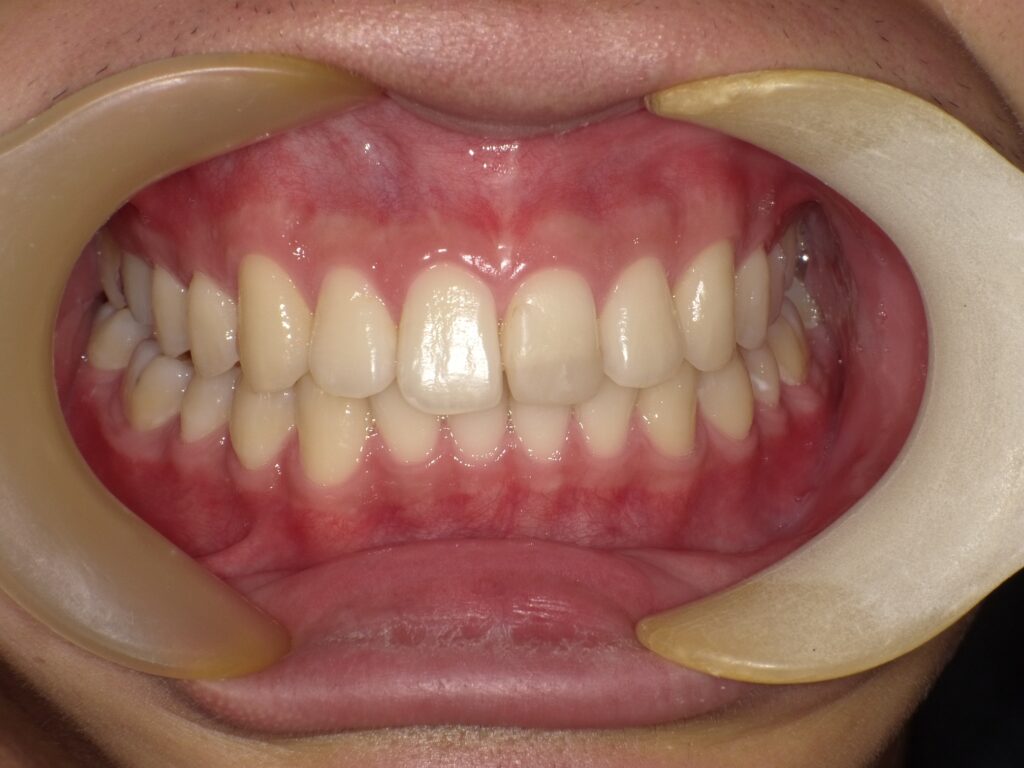

• 【治療後】

隙間がきれいに閉じ、自然な歯並びになっているのが分かります。